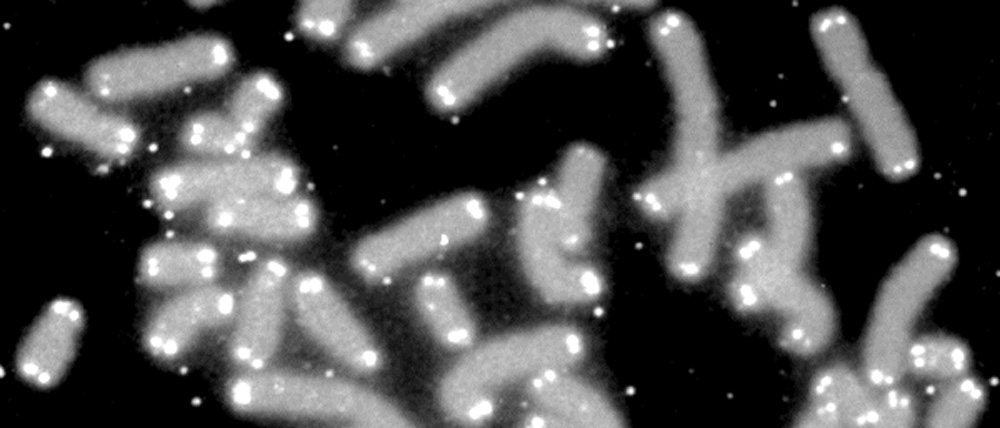

New study uncovers precise mechanism by which telomeres help prevent cancer-driving genetic changes

Scientists have worked out how a protective element of our DNA helps prevent an abnormal genetic event that can lead to cells becoming cancerous.